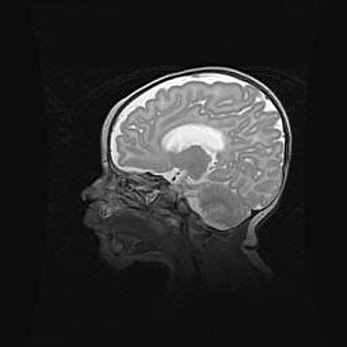

Лейкомаляция с кистозно-глиозной дегенерацией головного мозга.

Возраст: 2 месяца 25 дней

Вес: 6400 г

Окружность головы: 40 см

Срок гестации: 41 неделя

Лейкомаляцию относят к ишемически-гипоксическим повреждениям головного мозга, диагностируемым у новорожденных. При лейкомаляции в головном мозге обнаруживают очаги некроза, возникшие после тяжелой гипоксии и нарушения кровотока. В процессе морфогенеза очаги проходят три стадии: 1) развития некроза, 2) резорбции и 3) формирования глиозного рубца или кисты. Перивентрикулярная лейкомаляция (ПЛ) встречается примерно в 12% случаев среди новорожденных, обычно – у недоношенных детей, причем, частота ее зависит от массы, с которой младенец появился на свет. Наибольшее число малышей страдает лейкомаляцией, если масса при рождении 1500-2500 г.